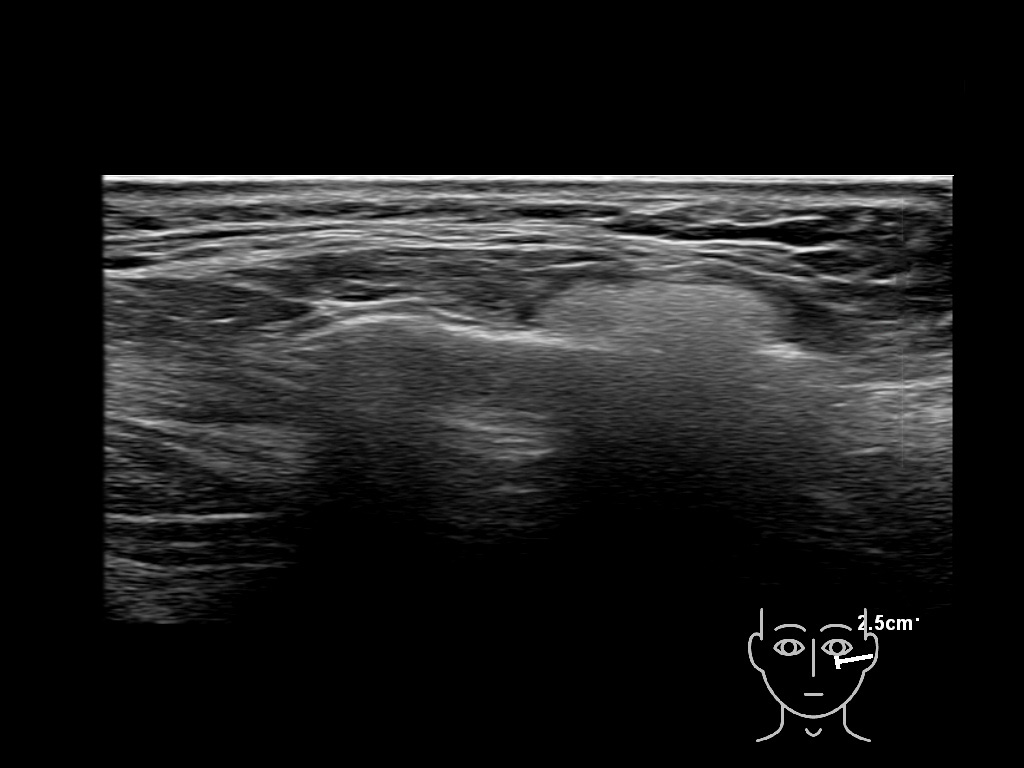

Draw in the image on the right where the fillers are located. To check if your answer is correct, please click on the secondary image.

Draw in the second image below where the fillers are located. To check if your answer is correct, swipe the first image to the right.